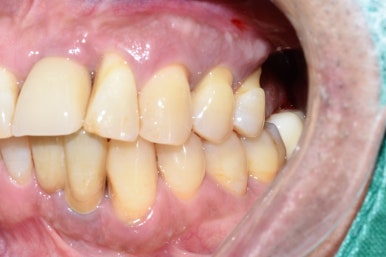

흔들리는 옆 치아와 흔들리는 임플란트를 제거하고 임플란트2개와 임플란트 브릿지로 마무리

흔들리는 옆 치아1개와 흔들리는 임플란트2개를 제거하고

3개의 자리를 임플란트2개와 가짜머리1개가 있는 임플란트 브릿지로

3개의 자리를 마무리하였습니다.

다른치과에서 몇년전에 한 인플란트가 흔들리고 붓는다고 온 분이었습니다.

그림에 1로 표시한 부분은 임플란트 주변을 감싸는 뼈가 많이 녹아서 흔들리고

2로 표시한 치아는 중간 연결고리나사가 부러져서 임플란트 머리도 같이 흔들리는 상태였습니다.

1과 2 임플란트 모두 제거하고

새로 임플란트를 심어 완성하였습니다.